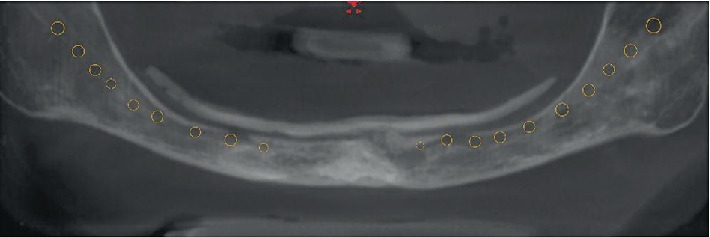

Панорамное изображение КЛКТ. Просвечивается нижнечелюстной канал. Отмечено отверстие сосудисто-нервного пучка под мягкими тканями.

КЛКТ-исследование выявило близкое расположение нижнечелюстного канала, при этом выход нижнего альвеолярного нерва через ментальные отверстия находился непосредственно под слизистой оболочкой, что подтверждалось жалобами пациентки. Ей были предложены варианты лечения с использованием дентальных имплантатов и костной аугментации. Пациентка отказалась от костной пластики и выбрала установку коротких имплантатов в переднем отделе нижней челюсти.

Далее была проведена оценка доступного объёма кости в переднем отделе нижней челюсти. В месте предполагаемой имплантации была отмечена локализация резцового канала, и пациентка была информирована об этом, включая возможные послеоперационные осложнения.

Четыре имплантата были виртуально размещены, из которых два установлены под углом 29 градусов из-за недостаточного объёма доступной костной ткани.

КЛКТ. Корональная проекция нижней челюсти. Четыре имплантата установлены в области зубов 3.2, 3.4, 4.1 и 4.3. Дистальные имплантаты наклонены на 29 градусов.